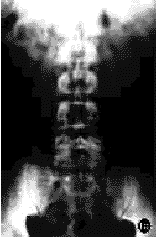

图2 术后6个月随访时,L4,5滑脱完全复位,骨痂生长良好,横突间植骨骨性融合 2a 术后X线正位片 2b 术后X线侧位片

本组21例,术后随访3~16个月,平均8.3个月。随访时症状完全消失者19例,临床满意率为90.5%(19/21),下腰痛症状完全改善率为84.6%(11/13),下肢疼痛改善率为100%(8/8),间歇性跛行改善率94.7%(18/19)。Ⅰ度滑脱完全复位率94.4%(17/18);Ⅱ度滑脱完全复位者2例,部分复位(70%)1例。本组21例滑脱完全复位率为90.5%(19/21)。2例部分复位者,1例术前因两个节段腰椎滑脱而行三个节段腰椎固定术,术后1年随访时,腰痛症状仅部分改善;另1例合并颈胸段椎管狭窄,其部分临床症状可能与此有关,术后6个月随访时,仍有部分跛行,为行颈胸椎MRI检查,取出SOCON内固定器,术中见固定节段融合良好,X线片显示无滑脱改变(图1,2)。本组无一例发生内固定失败。